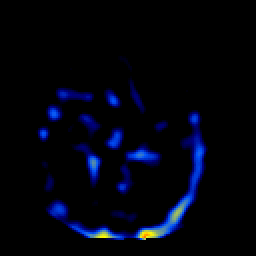

SPECT TL Study #2 -- Slice #27

[Home][Help][Clinical][Tour 1][Tour 2][Tour 3] Slice 27